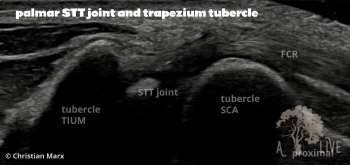

carpal ligaments